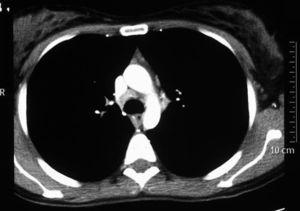

Mujer de 27 años de edad, a quien se valoró en el Servicio de Medicina Interna por fiebre diaria de 3 meses de evolución, de predominio vespertino, sudación nocturna y lesiones maculopapulares no pruriginosas. La exploración física era normal, sin que se apreciaran adenopatías cervicales ni supraclaviculares. La analítica no presentaba alteraciones. Se realizó aglutinación tífica y de Brucella, que fueron negativas, al igual que los anticuerpos contra el virus de Epstein-Barr, las pruebas reumáticas e inmunológicas y el Mantoux. En la tomografía computarizada toracoabdominal se objetivaron nódulos subpleurales de distribución periférica y pequeño tamaño, el mayor de 9mm de diámetro, en el pulmón derecho, discretas adenopatías paratraqueales e hiliares bilaterales, y una adenopatía subcarinal (figura 1). La fibrobroncoscopia fue normal. Se efectuaron biopsias transbronquiales, bronquiales, lavado broncoalveolar para citología y microbiología, sin hallazgos concluyentes. Se decidió efectuar una mediastinoscopia, en la que se observó un conglomerado ganglionar en la región 4R, del que se tomaron biopsias para microbiología y anatomía patológica. La microbiología fue negativa y el informe de anatomía patológica señaló linfadenitis reactiva con necrosis aneutrofílica, indicativa de enfermedad de Kikuchi. Al mes de la cirugía la paciente se encontraba afebril y asintomática.

Figura 1. Tomografía axial computarizada.